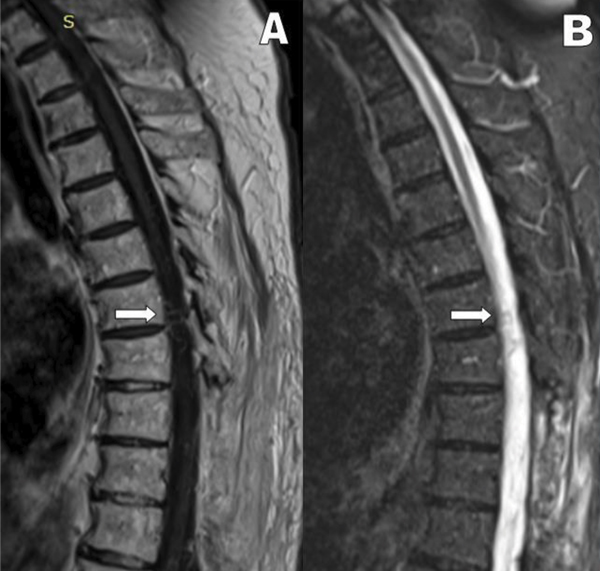

Paciente masculino de 75 años de edad, con antecedente de insuficiencia renal y canal estrecho lumbar, presentado clínicamente como lumbociatalgia bilateral con claudicación de la marcha a menos de 100 mts. Se realizó cirugía descompresiva con artrodesis L4-L5 a principios del 2021 en otra institución. El procedimiento se realizó sin complicaciones inmediatas y posterior alta institucional a los 5 días posquirúrgicos. A los 12 meses, el paciente nuevamente presentó cuadro progresivo de dolor lumbar similar al anterior, con predominio del componente ciático, más alteración de la marcha. Ante tal evolución, se decidió realizar una Resonancia Magnética Nuclear (RMN) dorsolumbar, donde se observó una hiperintensidad medular central en secuencia T2, que se extendía desde los últimos segmentos dorsales a los primeros lumbares (Figura 1). El cuadro se interpretó en ese momento como siringomielia, con exploración de la zona comprometida sin hallazgos relevantes y con muestra de anatomía patológica con posterior informe de edema medular.

Figura 1: RMN columna dorsal en secuencia T2 corte sagital y axial (A-B), revela hiperintensidad central (flecha)

El estudio diagnóstico inicial es la resonancia magnética nuclear espinal. Los principales diagnósticos fueron enfermedad degenerativa de la columna (50 % de casos), mielitis, enfermedad prostática (5 %) y enfermedad intramedular-tumor (4,5%)20. La presencia de una FAVd se caracteriza por una tríada de hallazgos en la resonancia magnética de rutina18,19,20,21. Primero una señal de hiperintensidad central medular en secuencia T2 es sugestivo de edema, presente en el 90% de los casos19,20,22. El edema puede ser focal o abarcar múltiples segmentos continuos; rara vez se encuentra en todo el cordón. Segundo, hallazgos en T2 de vacíos de flujo alrededor de la médula, especialmente dorsal, representan venas congestionadas18,19, presentes en el 80% de los casos20. Tercero, la presencia de realce dentro del cordón en secuencia T1 posteriores al contraste30. Hallazgos compatibles con los estudios por imágenes presentados en la descripción de este caso y realizada en primera instancia para descartar otras patologías.